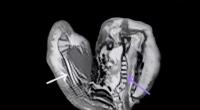

A córnea é um tecido fino e transparente, situado na região anterior do globo ocular, cuja função é refratar e transmitir a luz. É possível transplantar apenas uma parte desse tecido, que é dividido em cinco camadas: epitélio, membrana de Bowman, estroma, membrana de Descemet e endotélio.

Em geral, o transplante ocorre quando há mudança na curvatura, ruptura da membrana e opacidade. Alguns casos podem ser sanados com apenas uma fina camada do endotélio. Isso será possível a partir da implantação da técnica cirúrgica pelos centros transplantadores.

“O transplante penetrante é preconizado em casos em que todas as partes da córnea foram danificadas. Mas caso a visão do paciente tenha sido afetada por Ceratocone, doença que afeta a região anterior e o estroma corneano, é indicado o transplante lamelar, que substitui apenas uma parte da córnea. Já a ceratopatia bolhosa e a distrofia Fuchs acometem o endotélio e a membrana de Descemet, portanto é recomendado o transplante de córnea endotelial. Todas as possibilidades cirúrgicas continuarão a ser ofertadas”, explicou o oftalmologista.